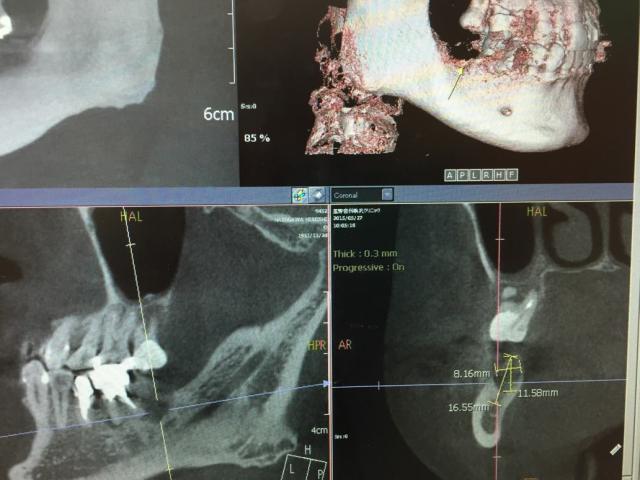

今日のインプラント手術は欠損部の骨の条件がよかったのでフラップレス法で痛みと腫れをなくす方法で行っています。